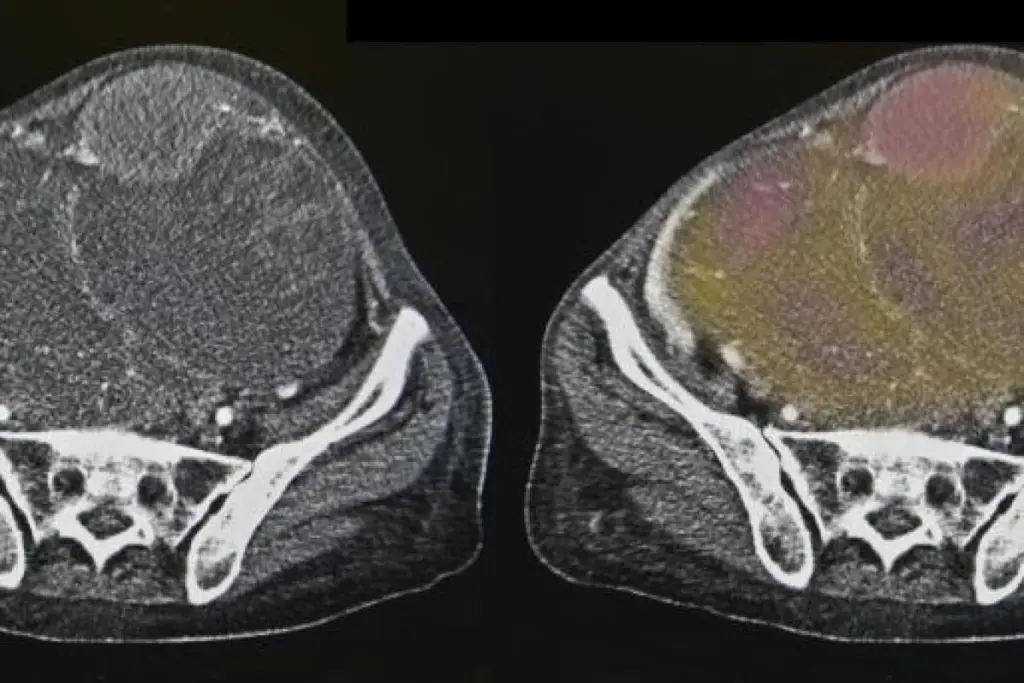

Transvaginal Ultrasound (TVUS): A Primary Screening Tool

Transvaginal ultrasound (TVUS) is key in checking for ovarian cancer. It’s a way to see the ovaries clearly. This helps doctors find any problems.

How TVUS Works

TVUS uses an ultrasound probe in the vagina. It sends sound waves to make detailed images of the ovaries. This method is more precise than traditional ultrasound.

The images from TVUS help doctors spot issues like cysts or tumors. They can also see the size and shape of these growths.

What TVUS Can and Cannot Detect

TVUS is great at finding ovarian problems, like cysts and masses. But, it can’t tell if a tumor is cancerous or not. It gives info on size and shape, but can’t say for sure if it’s cancer.

Even with its limits, TVUS is a key part of ovarian cancer screening. It’s often used with other tests, like the CA-125 blood test, for a full check.